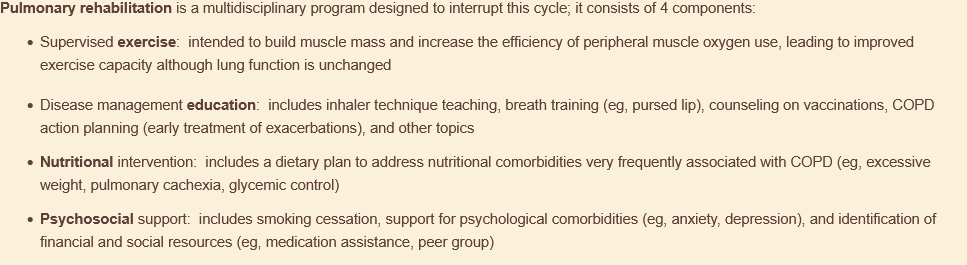

what is the most strongly indicated thing to improve a patient w/ copd’s ability to perform ADLs & reduce risk of copd-related hospitalizations?

pulmonary rehab!